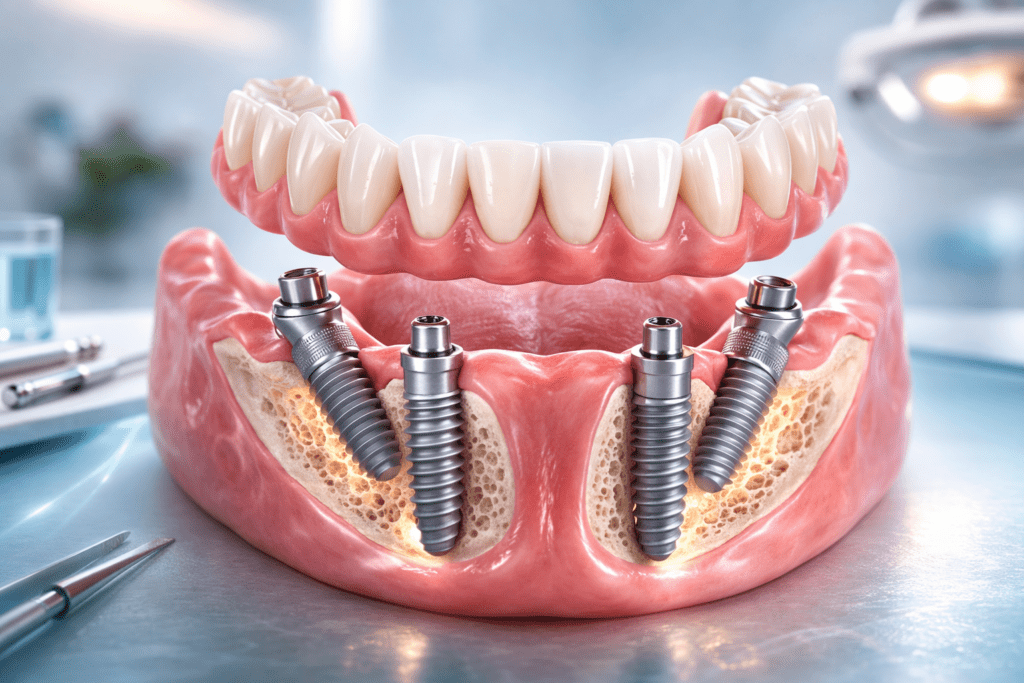

All-on-4 (Барлығы 4-те) – толық тіссіз қалған (немесе қалған тістері жұлуға жататын) жақ сүйекке небәрі 4 титан имплантын орнатып, оған тұтас көпіртәрізді протезді бекіту технологиясы. Алдыңғы екі имплант түзу, ал артқы екі имплант 30-45 градус бұрышпен орнатылады. Бұрышпен орнату сүйек ауданын максималды пайдалануға және көп жағдайда қосымша сүйек өсіру (синус-лифтинг) операциясынан аулақ болуға мүмкіндік береді.

Егер дәрігер 4 имплантты кездейсоқ немесе түзу етіп қана қойса, ол All-on-4 халықаралық хаттамасына жатпайды. All-on-4 концепциясының басты ерекшелігі – артқы импланттардың бұрышпен (дистальді көлбеу) орнатылуы және арнайы мультиюнит (multi-unit) абатменттердің қолданылуы. Мультиюнит – бұрышпен тұрған импланттың осін түзететін аралық бөлшек. Осының арқасында протез қишық орнатылған импланттарға тікелей және тегіс бұралып бекітіледі. Бұл биомеханикалық тұрғыдан шайнау жүктемесін 4 нүктеге біркелкі таратуға мүмкіндік береді.

- Хирургия: Жергілікті анестезия немесе седация (дәрілік ұйқы) астында жарамсыз тістер жұлынып, 4 имплант (2 тік, 2 бұрышты) орнатылады. Хирург мультиюнит абатменттерді бекітеді.